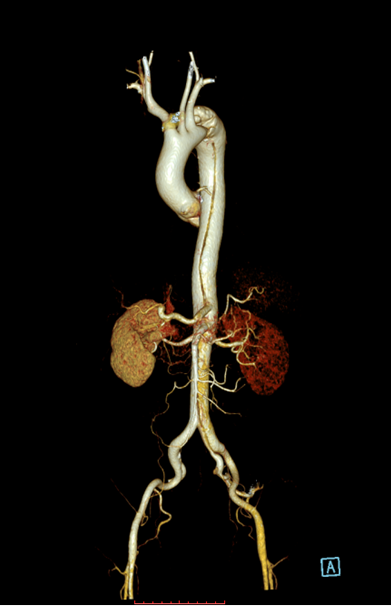

患者以“突发胸背部疼痛1月余”为主诉急诊入住中南大学湘雅二医院血管外科,入院后经过CTA确诊为“主动脉夹层”,夹层第一破口紧邻左锁骨下动脉,且左锁骨下动脉起始部呈局限性夹层样改变,胸主动脉真腔全程受压,病情十分危重,患者疼痛难忍!

经过仔细测量及讨论,根据患者夹层真腔受压严重、近端锚定区不足,左锁骨下动脉累及到血管根部以及病情比较危重的特点,舒畅教授决定使用目前已开展的临床试验研究项目(PATENCY study/NCT03767777)“先健新型主动脉弓烟囱支架”,该研究是先健科技公司与舒畅教授合作研发的新型主动脉弓烟囱支架,对于累及弓上分支的主动脉夹层、且病情比较紧急的患者具有明显的优势!

先健科技的新型主动脉弓烟囱支架适用于累及主动脉弓的胸主动脉夹层,产品由Ankura™ Pro主动脉主体覆膜支架系统和Longuette™主动脉分支覆膜支架系统组成。

术中通过DSA造影显示:主动脉夹层破口位于左锁骨下动脉近端,真腔压闭!舒畅教授为患者完美的实施TEVAR+左锁骨下动脉裙边烟囱支架置入术,手术过程非常顺利,胸主动脉支架释放良好,患者的主动脉夹层破口封闭良好,真腔打开良好,左锁骨下动脉释放的裙边支架血流通畅,没有内漏发生。